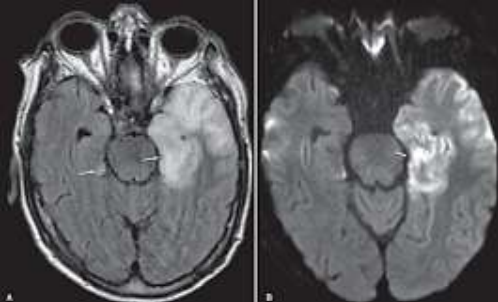

Paciente de 8 anos, com histórico de febre, cefaléia, crises convulsivas reentrantes e rápida progressão para rebaixamento do nível de consciência. Realizada punção lombar que demonstrou celularidade elevada com predomínio de linfócitos com glicose e proteínas normais. Realizou ressonância magnética do crânio que demonstrou os achados abaixo.

Baseado no caso clínico e nos achados de imagem, assinale a alternativa correta.